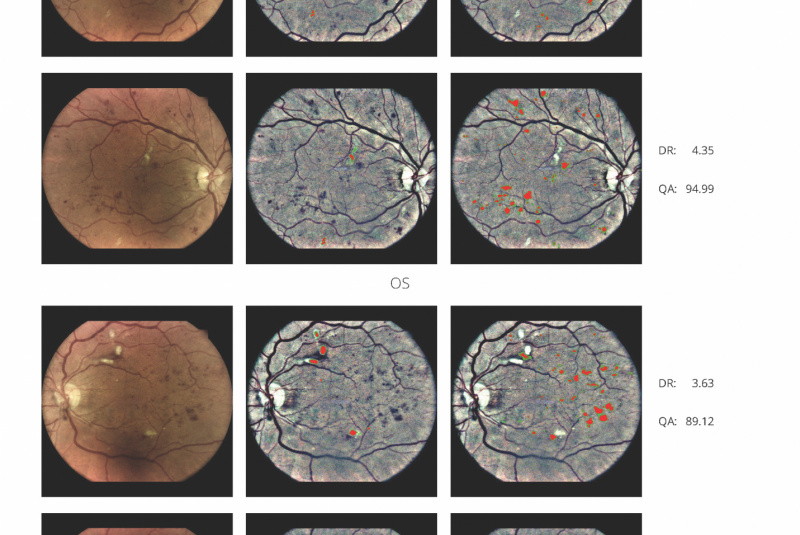

AI (umělá inteligence) okamžitě rozpozná práznaky diabetické retinopatie a klasifikuje výsledky podle závažnosti na základě mezinárodních klasifikací. Získáte přehled s hodnocením závažnosti záchytu, kde po analýze snímků zachycených kamerou iCare DRS Plus je automaticky generován report o pacientovi se stupnicí závažnosti pro diabetickou retinopatii na základě mezinárodních standardů (ICDR, AREDS).

Fundus kamera iCare DRSplus pořídí celkem 4 vysoce kvalitní True Color snímky (dva z pravého a dva z levého oka), které se automaticky ukládají na cloud a posílají se na zpracování AI - umělé inteligenci. Report je dostupný ihned a ten je možno konzultovat s pacientem během téže návštěvy u lékaře.